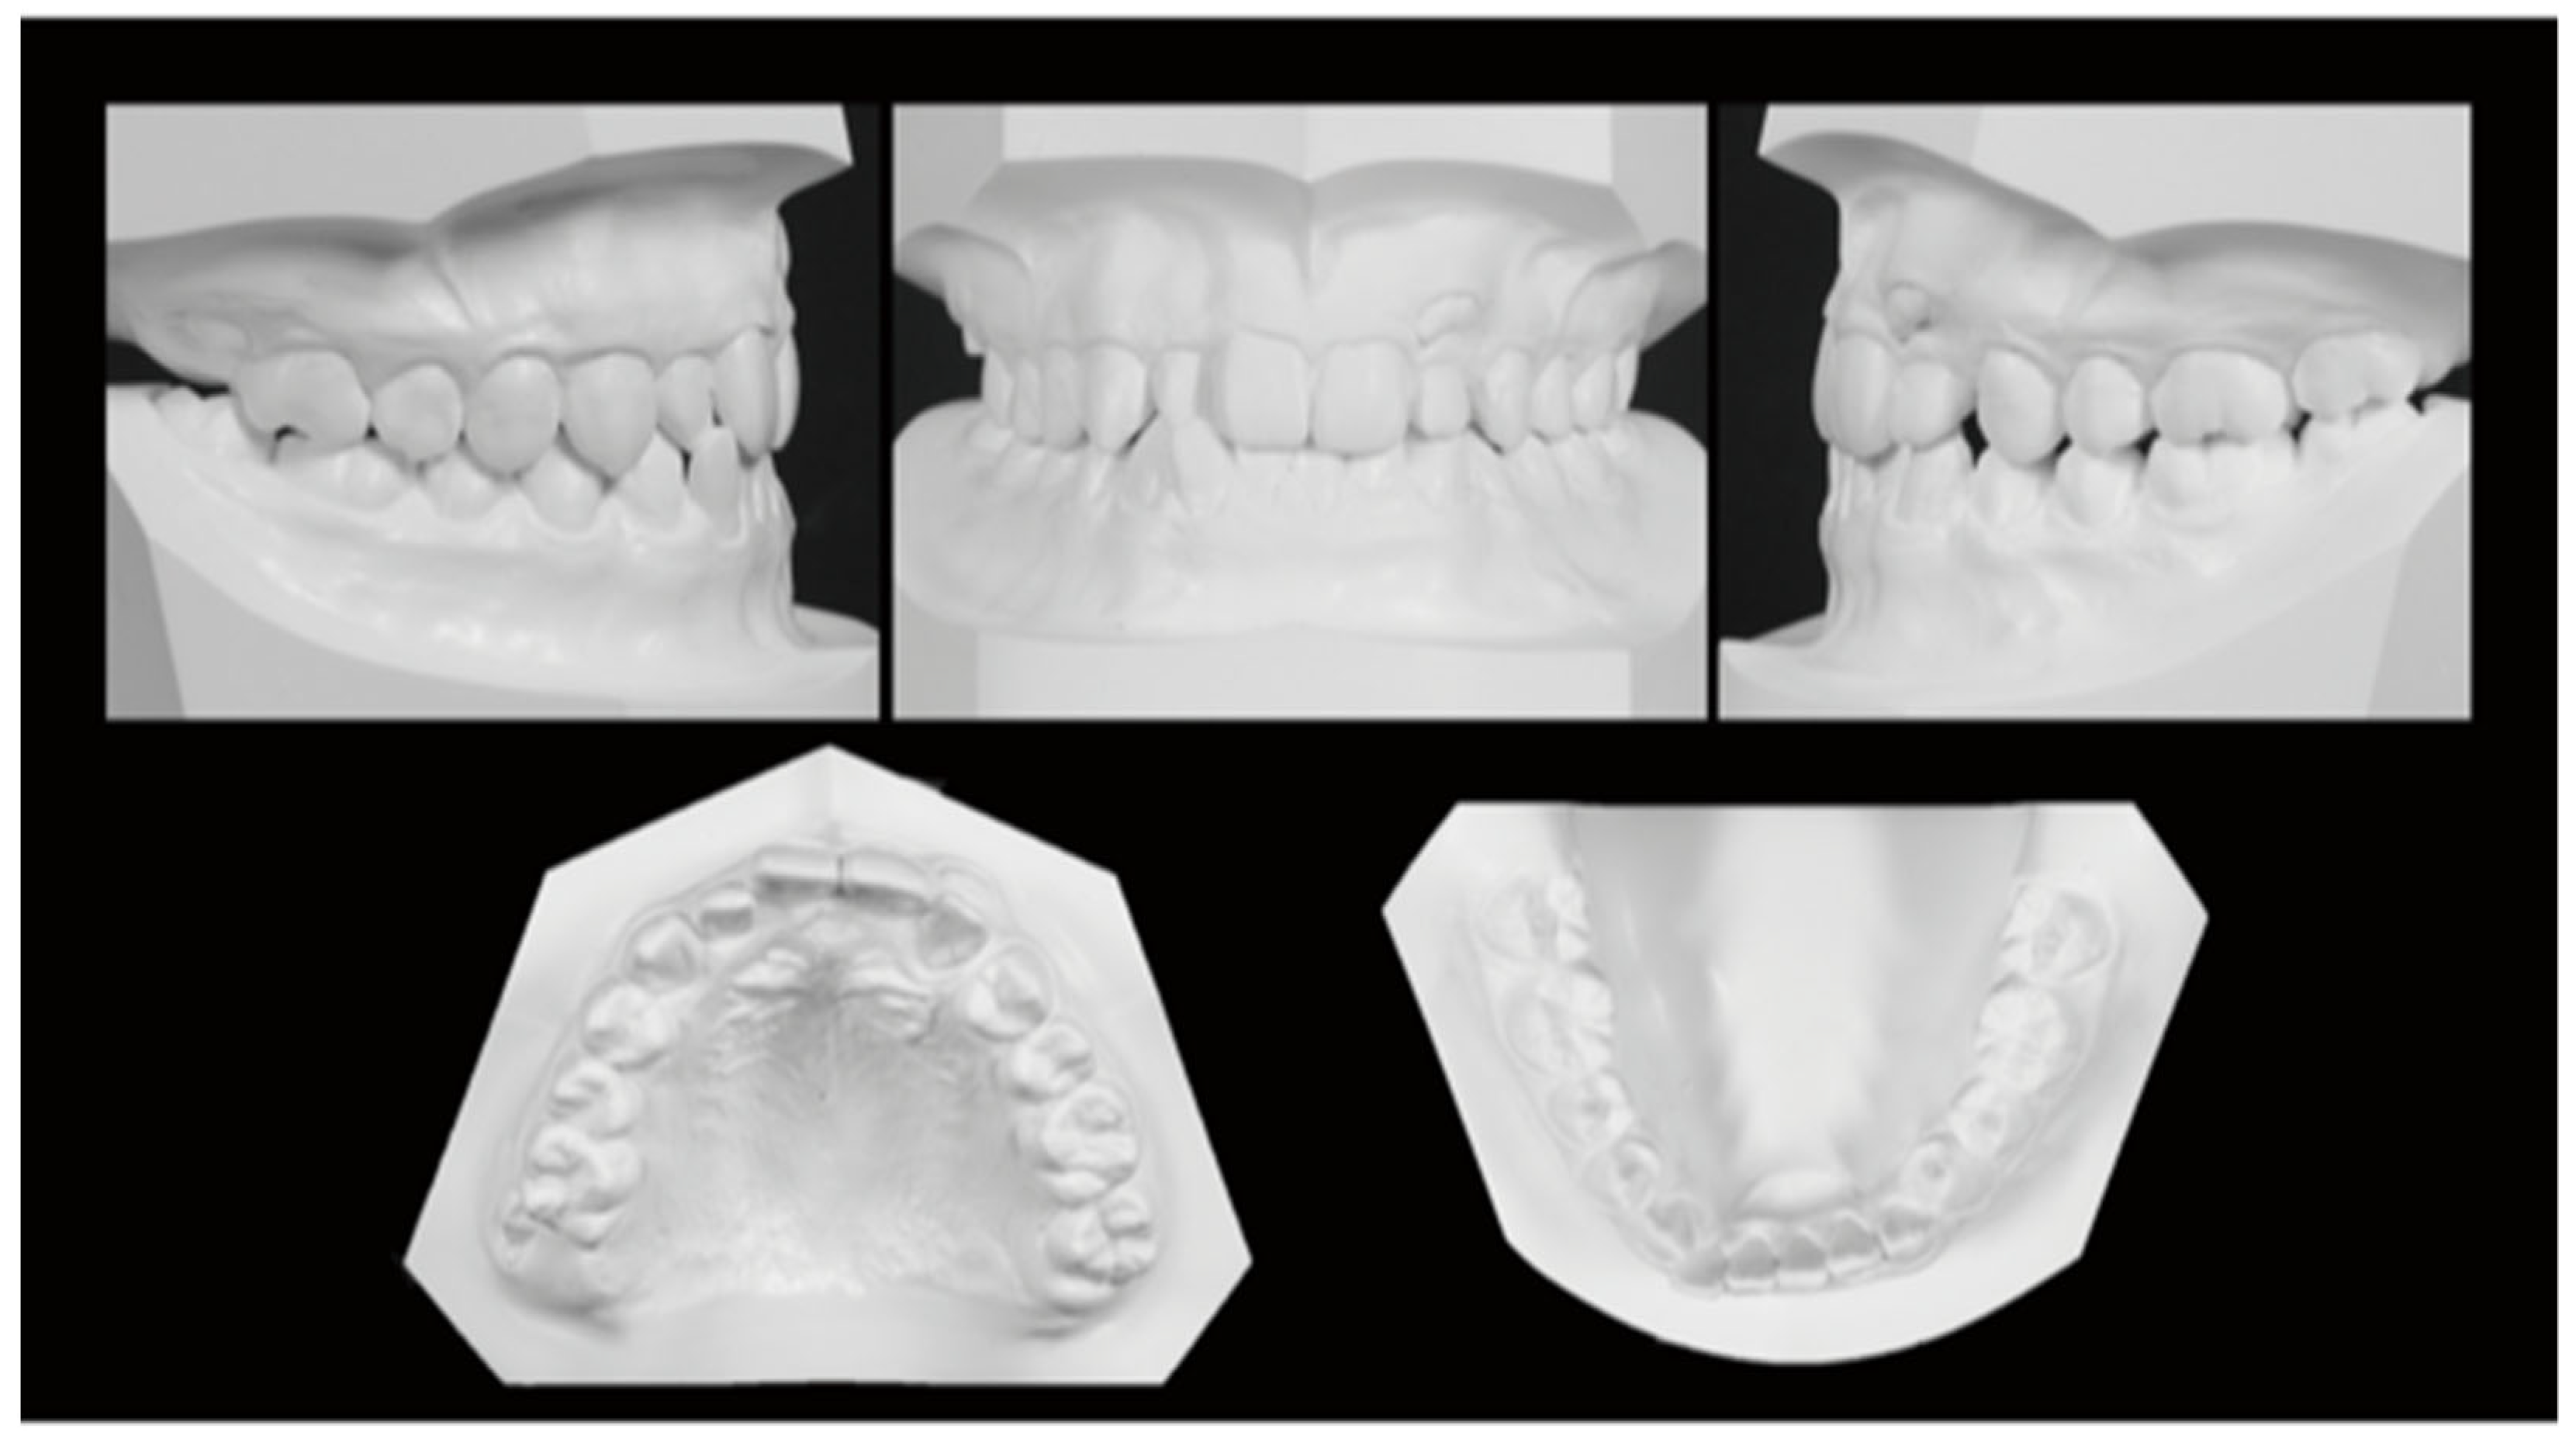

Figure 8. Dental casts. (A) At termination of active treatment (age, 17 years 9 months). (B) At completion of eruption of the maxillary left third molar (age, 21 years 3 months).

In the frontal view, the midline deviation seen at the initial presentation was corrected, with the maxillary and mandibular midlines aligned with the facial midline. In the lateral view, a good E-line was maintained. The occlusal relationship of the first molars was Angle Class I on both sides, demonstrating close occlusion. The maxillary left canine that had shown eruption disturbance was aligned in the dental arch. The maxillary left third molar naturally erupted and occluded with the mandibular left second molar. The maxillary and maxillary anterior teeth were in an appropriate covering relationship (Figure 7 and Figure 8).